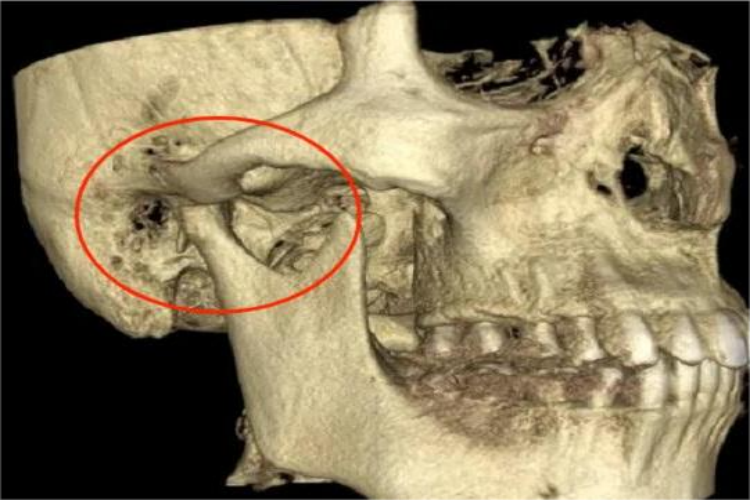

颞颌关节:颞颌关节间隙位于关节凹和髁状突之间,呈低密度影,关节间隙宽度在2mm以上,上间隙最宽,后间隙次之,前间隙最窄,两侧相等。髁状突呈椭圆形密度高的影像,由连续、整齐、致密白线围绕。开口位时,髁状突位于关节结节下方或前下方,闭口位髁状突位于关节凹内。

颌面部CT对于颌面部组织病变的发现、诊断及其范围确定等,均有重要价值。比如通过CT下腮腺腺体形态、大小和密度的变化,可以判断病变的部位及蔓延范围,良性肿瘤与恶性肿瘤的鉴别,以及腮腺外肿瘤的侵犯。

若有良性肿瘤,其CT特征是肿块多呈类圆形,边缘光整,密度均匀,其中血管瘤有明显强化。恶性肿瘤的形态多不规则,边界模糊,密度不均匀,肿块内常有出血、坏死或囊变,常侵犯周围软组织及脂肪间隙,颅底骨质破坏及淋巴结转移。